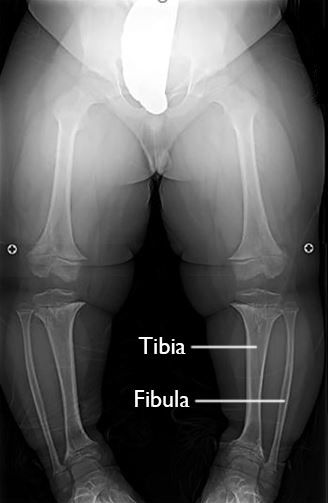

X-ray of bowed legs

X-ray of an 8-year-old boy with achondroplasia shows bowing of the lower legs. Note that the patient’s fibula is longer than his tibia. This overgrowth of the fibula is typical of achondroplasia.

Reproduced from Carter CW, Sharkey MS: Contemporary management of the pediatric patient with achondroplasia. Orthopaedic Knowledge Online Journal 2014; 12(1). Accessed July 2018.